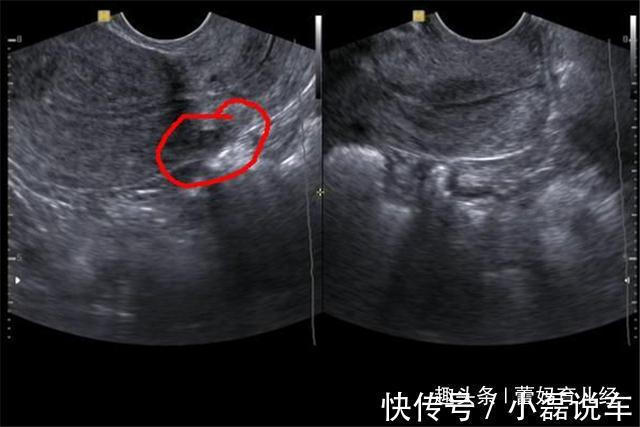

文|蕾妈育儿经(专注优质原创文章,拥有本文章版权,欢迎转发分享)养一个孩子不容易,从怀孕那一刻母亲就要注意很多细节,吃喝玩乐不能再像以前一样,稍有不慎就会导致胎儿死亡。我们都知道怀孕最关键的时期是前期,前3个月要是稳定了,胎儿流产的几率就会降低,但这不是说胎儿越往后就会越安全,母亲的行为直接影响着孩子能否安全降生。小玲平时就非常嘴馋,但怀宝宝的时候家里人管的很严,所以说馋了很久。怀孕7个月的时候,正巧遇到了同事聚会,小玲就借此机会大吃一顿,瞒着丈夫烤肉和海鲜吃了很多,但也正是因为这一顿聚餐,小玲被弓形虫感染,导致宝宝停止了胎动,最后被迫去医院做了引产,因为过于悲愤,小玲得了抑郁症。

3、饮食与精神问题孕妇怀孕期间免疫力低,如果经常吃烤肉和海鲜就容易被弓形虫感染,就算没有感染,一旦腹泻也容易流产,虽说这是偶然性的,但各位宝妈不要像小玲那样有侥幸心理。此外像焦虑和睡眠不好等精神问题会导致免疫功能紊乱,胎儿缺氧就会出现胎心停止等问题。